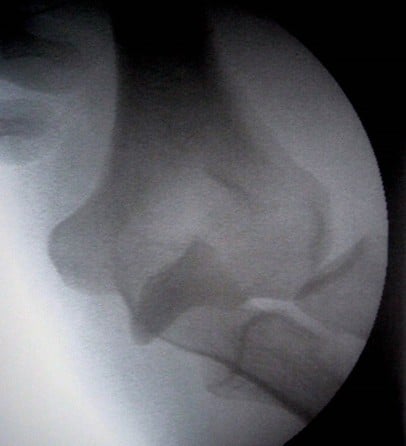

Luxations complexes

Terrible triade du coude associant

Dans ce cas la chirurgie est quasiment toujours nécessaire du fait de l’instabilité du coude.

Il est interdit dans ce contexte de faire une résection de tête radiale : soit ostéosynthèse soit prothèse de tête radiale. Sinon grande instabilité.